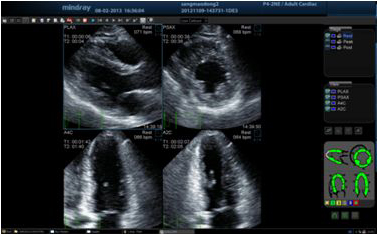

Стресс-эхокардиография

Обеспечивает точное измерение функции миокарда в ответ на внешний стресс или лекарственный препарат.